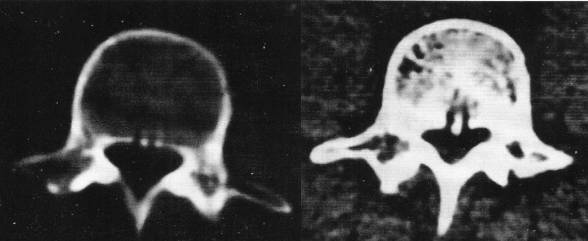

3、CT检查:可取之处在于可准确显示异常组织的性质,直接显示椎间盘突出的真实性质和范围。可清楚地显示椎管横断面的骨性结构,对侧隐窝狭窄,黄韧带肥厚,椎间关节病变及神经孔周围极外型椎间盘突出的显示有独特的临床价值。

但此检查不足之处在于对软组织分辨率低,不能直接进行矢状面、斜面扫描。对纤维环膨出显示较模糊,有假阳性情况。

椎体后方静脉孔处的骨质间隔,不要误认为后纵韧带骨化

椎管狭窄并间盘突出

椎管狭窄

中央性椎管狭窄

侧隐窝狭窄